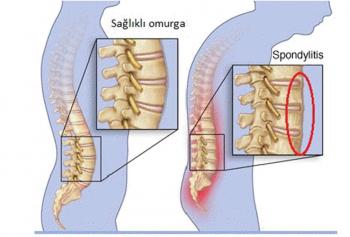

Duruş bozukluklarının fiziksel ve ruhsal olarak birçok soruna yol açabileceğini belirten Fiziksel Tıp ve Rehabilitasyon Uzmanı Dr. Esin Selimoğlu, yanlış duruş pozisyonlarının, boy kısalmasına dahi neden olabileceğini söyledi.